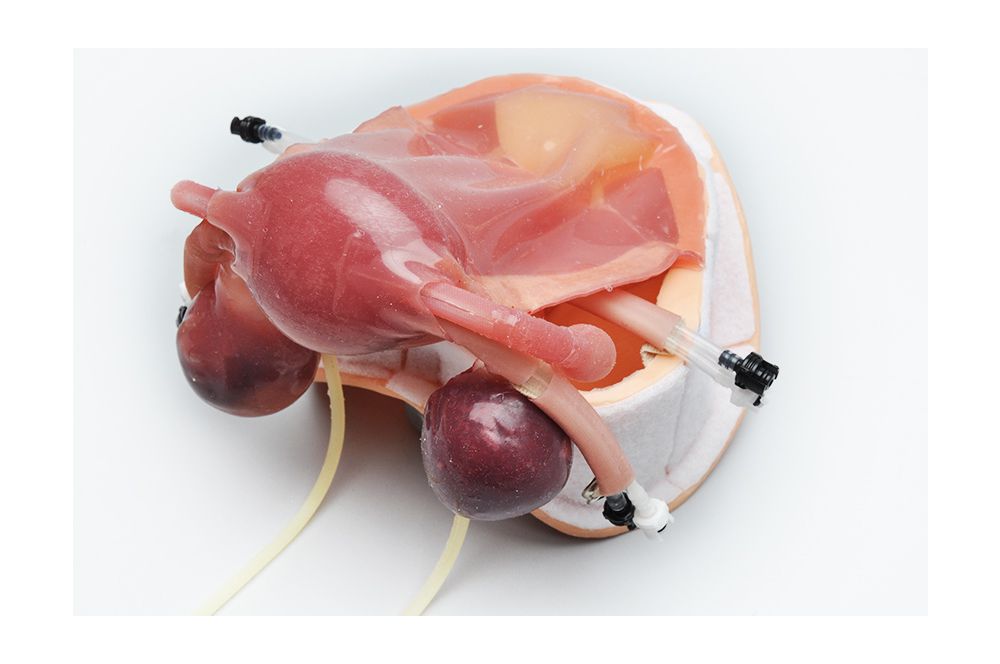

Анатомия женского организма: строение и функции матки